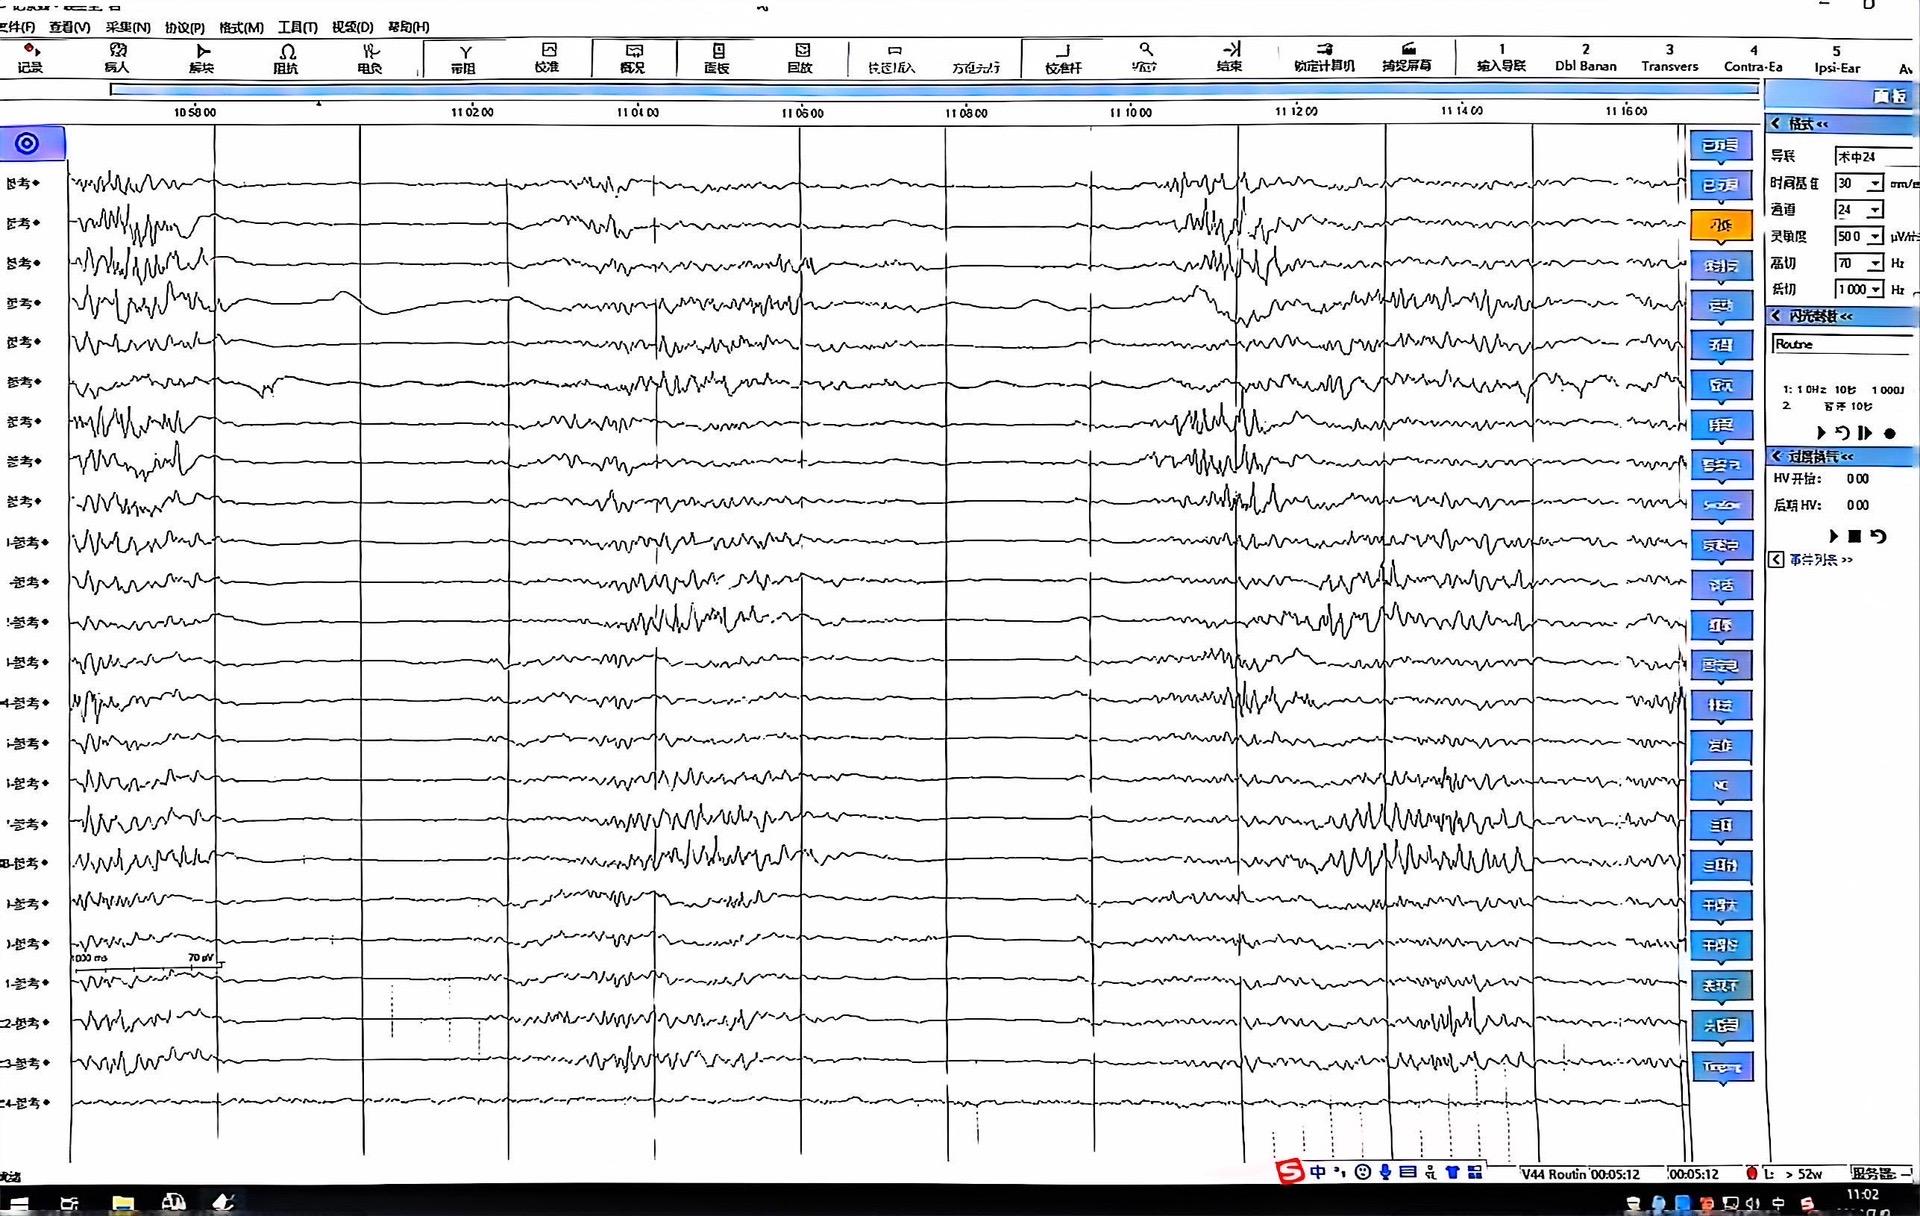

脑内血管瘤合并癫痫。其实海绵状血管瘤如果在非功能区手术难度一般,但是如果合并癫痫单纯切除海绵状血管瘤,术后还是可能发作,建议多手段联合,按癫痫来评估和手术,而非按肿物来评估,这和低级别胶质瘤并癫痫是一样的,单纯切除肿瘤的话癫痫控制可能不理想!